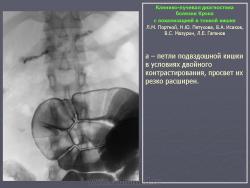

В дифференциально-диагностическом плане интересно -